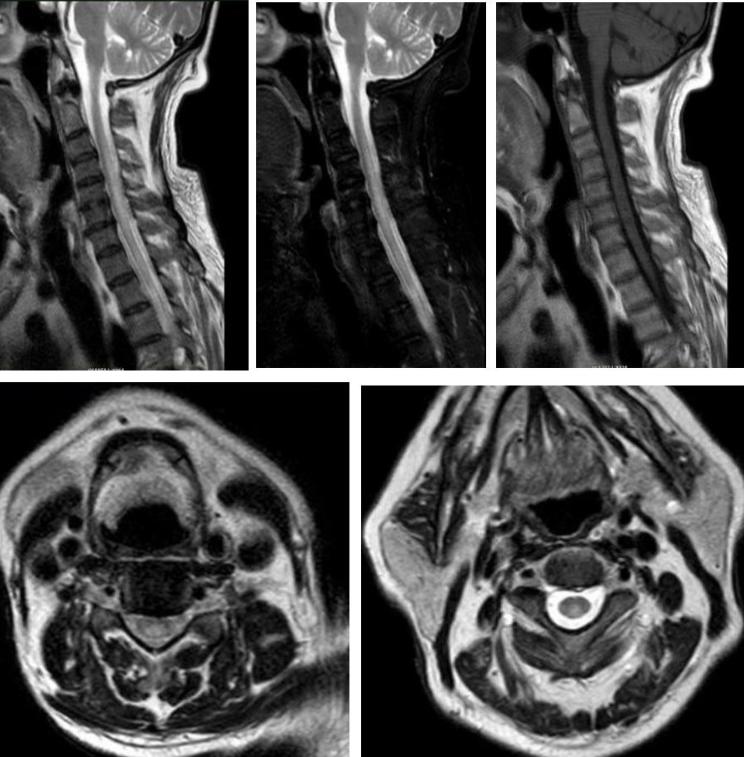

男性34岁,肢体麻木无力1月余入院。查体:神志清,双上肢肌力5级,双下肢4+级,远端4级,左上肢触觉轻度减退,双下肢触痛觉,振动觉明显减退,外院激素冲击治疗5天症状无改善。

答案:脊髓亚急性联合变性。维生素B12摄取、吸收、结合与转运的任何一个环节出现障碍均可引起维生素B12缺乏。内因子抗体和(或)抗胃壁细胞抗体阳性的SCD患者需要长期肌肉注射维生素B12。笑气中毒也是脊髓亚急性联合变性的重要原因,需要注意个人生活接触史。除了经典的反兔耳征/八字征/倒Ⅴ字征,脊髓亚急性联合变性还可以表现为圆点征、小字征、三角征。脊髓亚急性联合变性还需要与铜缺乏性脊髓病、维生素E缺乏性脊髓病、艾滋病相关性脊髓病鉴别。

老年女性,急性起病,突发颈后部疼痛伴右侧肢体麻木无力,右侧肢体肌力2级。

答案:脊髓硬膜外血肿。补充病史既往长期服用华法林。患者临床以麻木,肢体无力卒中样起病。但是有颈部疼痛病史,病史跟影像提示脊髓硬膜外血肿。脊髓硬膜外血肿可能是自发的,也可能是继发于创伤、凝血功能障碍或麻醉操作。危险因素包括高龄、女性、创伤、血管畸形、抗凝治疗和高血压。提醒注意的是这样的患者有可能在绿色通道中被当做急性卒中患者被溶栓。

男性68岁,四肢末梢麻木2月余,伴有站立不稳,加重1周,不能独立行走。查体双侧跟膝胫试验欠稳准,双侧位置觉、震动觉减退。

答案:脊髓亚急性联合变性。患者老年男性,亚急性病程,以深感觉受累为主要表现,脊髓影像长节段病灶,轴位显示后索病灶“圆点征”,颅内影像改变无特异性,NMOSD相关抗体检测以及OB均阴性。其特征性影像有“圆点征”、“小字征”、“三角征”、“八字征”等。